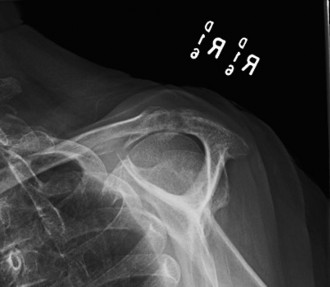

Treat a patient with infected total shoulder arthroplasty? CASE 21 A 70-year-old, right-hand-dominant female presents to clinic complaining of 4 years of gradually worsening chronic right shoulder pain and stiffness. She says the pain is worse at night and with any range of motion, denies a history of trauma, pain in other extremities, or numbness or tingling of the right upper extremity. She notes that her mother suffered from rheumatoid arthritis that affected her shoulder. Physical examination reveals decreased muscle bulk over the right supra- and infraspinatus fossae compared to the contralateral side, limited active and passive ROM, marked weakness with external rotation, and 4+/5 strength with shoulder abduction. X-rays of the right shoulder are shown in Figures 2–58 and 2–59.

Figure 2–58

Figure 2–59

The correct answer is (C). Rotator cuff tear arthropathy consists of a combination of rotator cuff insufficiency, glenohumeral joint degenerative changes, and superior humeral head migration. It is more common in women and also more often found on the dominant side. The patient’s clinical examination with weakened external

rotation and muscle atrophy signaling incompetent supra- and infraspinatus muscles point to rotator cuff insufficiency, and her plain films reveal narrowed glenohumeral joint space as well as superior migration of the humeral head. Choice D is incorrect because, while radiographs would show narrowing of the glenohumeral joint space, they would also likely show numerous osteophytes and posterior wear of the glenoid. Choice B is incorrect because, while adhesive capsulitis does present as decreased active and passive range of motion, the patient’s constellation of symptoms pointing towards rotator cuff insufficiency along with the radiographs make cuff tear arthropathy the more likely choice. Finally, Choice A is incorrect because even though she has a positive family history of rheumatoid arthritis, it is less likely to present only in a single joint. Also, rheumatoid arthritis on radiography appears more as an erosive process without the characteristic superior migration of the humeral head.